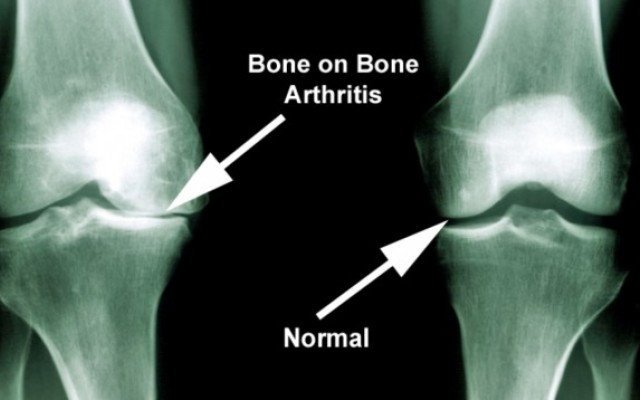

If you’re thinking about having knee replacement surgery, you’re in good company. Every year, more than a 55000 Australians opt for the procedure.

Many people have knee replacements (also called knee arthroplasty) because they have osteoarthritis. This condition occurs when the cartilage (tissue) that cushions the knee joint wears away. As a result, bone...